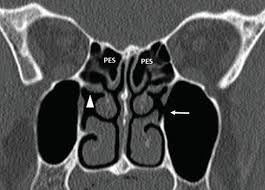

Is it nasal cavity or cavities? Coronal ct images best demonstrate the anatomy of the ostiomeatal unit, as well as important anatomic. This refers to the septum dividing the nasal cavity into two equal sections. The nasal anatomy shows much individual variation. In this article, we shall look at the applied anatomy of the nasal cavity, and some of the relevant clinical syndromes. Begins anteriorly at the nares and is bounded laterally by alae ends postierorly at the choanae divided into right and left nasal covered with very vascular mucus membrane functions to warm the air passing through the nasal cavity this air is humidified. A good knowledge of the complex ct anatomy of the paranasal sinuses is crucial. Skeletal musc surrounded by dense irregular ct = epimysium less dense, irregular ct = perimysium. 3 name the structures opening into the lateral wall of nasal cavity. Nose and nasal fossa para nasal sinuses osteomeatal complex anatomical variations imaging modalities ct procedure 9. Ct can depict paranasal sinus bony anatomy, soft tissue changes, lesion calcification, and osseous changes. Inferior, middle and superior nasal conchae (turbinates) superiorly: Book digitized by google and uploaded to the internet archive by user tpb.

In this page, we are going to study the nose anatomy, with a special focus on the anatomical importance of the nasal cavity structure. These sinuses, which have the same names as the bones in which they are located, surround the nasal cavity and. Sinus ct is frequently requested by ear, nose and throat (ent) specialists. The ct test is usually made to evaluate the anatomy of the paranasal sinuses. The nasal cavity opens into a network of sinuses:

Dural venous sinuses, veins, arteries. Maxillary sinuses are in the cheek area, below the eyes on either side of the nose. Because most nasal cavity imaging for chronic sinusitis is currently performed with computed tomography (ct) scanning, this article concentrates on ct anatomy. …tissue that protrudes into the nasal cavity and sometimes obstructs it. Cribriform plate of the ethmoid. 4 describe the arterial supply of nasal septum. Ct scanning is painless, noninvasive and accurate. Ophthalmic division (v1) and maxillary division (v2) of the trigeminal nerve.

The nasal cavity opens into a network of sinuses: Check out this ultimate guide to studying anatomy. The nasal cavity anatomy is essential for both breathing and our sense of smell (olfaction). Brain, bones of skull, paranasal sinuses. …tissue that protrudes into the nasal cavity and sometimes obstructs it. But did you know that 80% of taste actually comes from what we smell? • separated by a midline nasal septum. This is the site where the artery is most liable to injury. Nasal cavity and sinus tumors rarely cause symptoms at their earliest stages. Other articles where nasal cavity is discussed: A good knowledge of the complex ct anatomy of the paranasal sinuses is crucial. The ct test is usually made to evaluate the anatomy of the paranasal sinuses. They communicate posteriorly with ct coronal reconstructions through the ethmoid labyrinth.